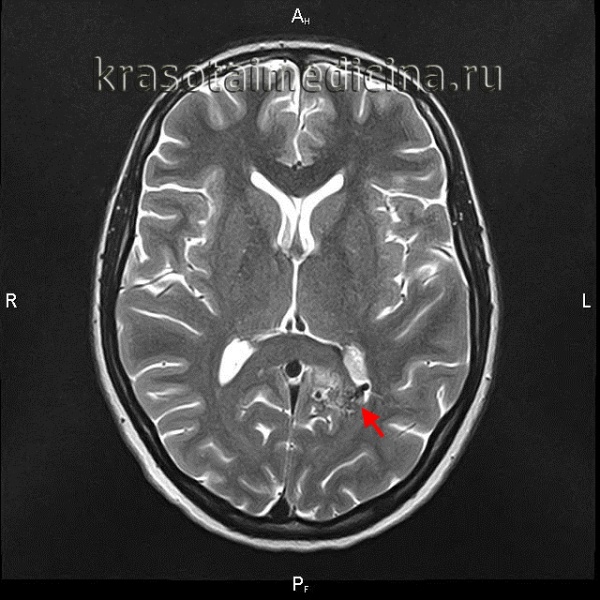

(Слева) Сагиттальный срез, Т2-ВИ: признаки острого массивного геморрагического пропитывания паренхимы спинного мозга на фоне исходно существовавшей кавернозной мальформации. Видны признаки распространенного отека спинного мозга выше и ниже кровоизлияния.

(Справа) На сагиттальном Т1-ВИ с КУ у этого же пациента отмечается более локализованное «пятнистое» контрастное усиление кавернозной мальформации, которая является причиной массивного кровоизлияния в паренхиму спинного мозга. Зона кровоизлияния в этом режиме исследования видна плохо, однако видны признаки диффузного увеличения объема спинного мозга.